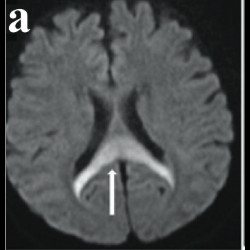

Wine Glass Sign and Empty Delta Sign: A Rare Imaging Presentation of Postpartum Encephalopathy in Dehydration

Wine Glass Sign and Empty Delta Sign: A Rare Imaging Presentation of Postpartum Encephalopathy in Dehydration

Wine Glass Sign and Empty Delta Sign: A Rare Imaging Presentation of Postpartum Encephalopathy in Dehydration

Wine Glass Sign and Empty Delta Sign: A Rare Imaging Presentation of Postpartum Encephalopathy in Dehydration